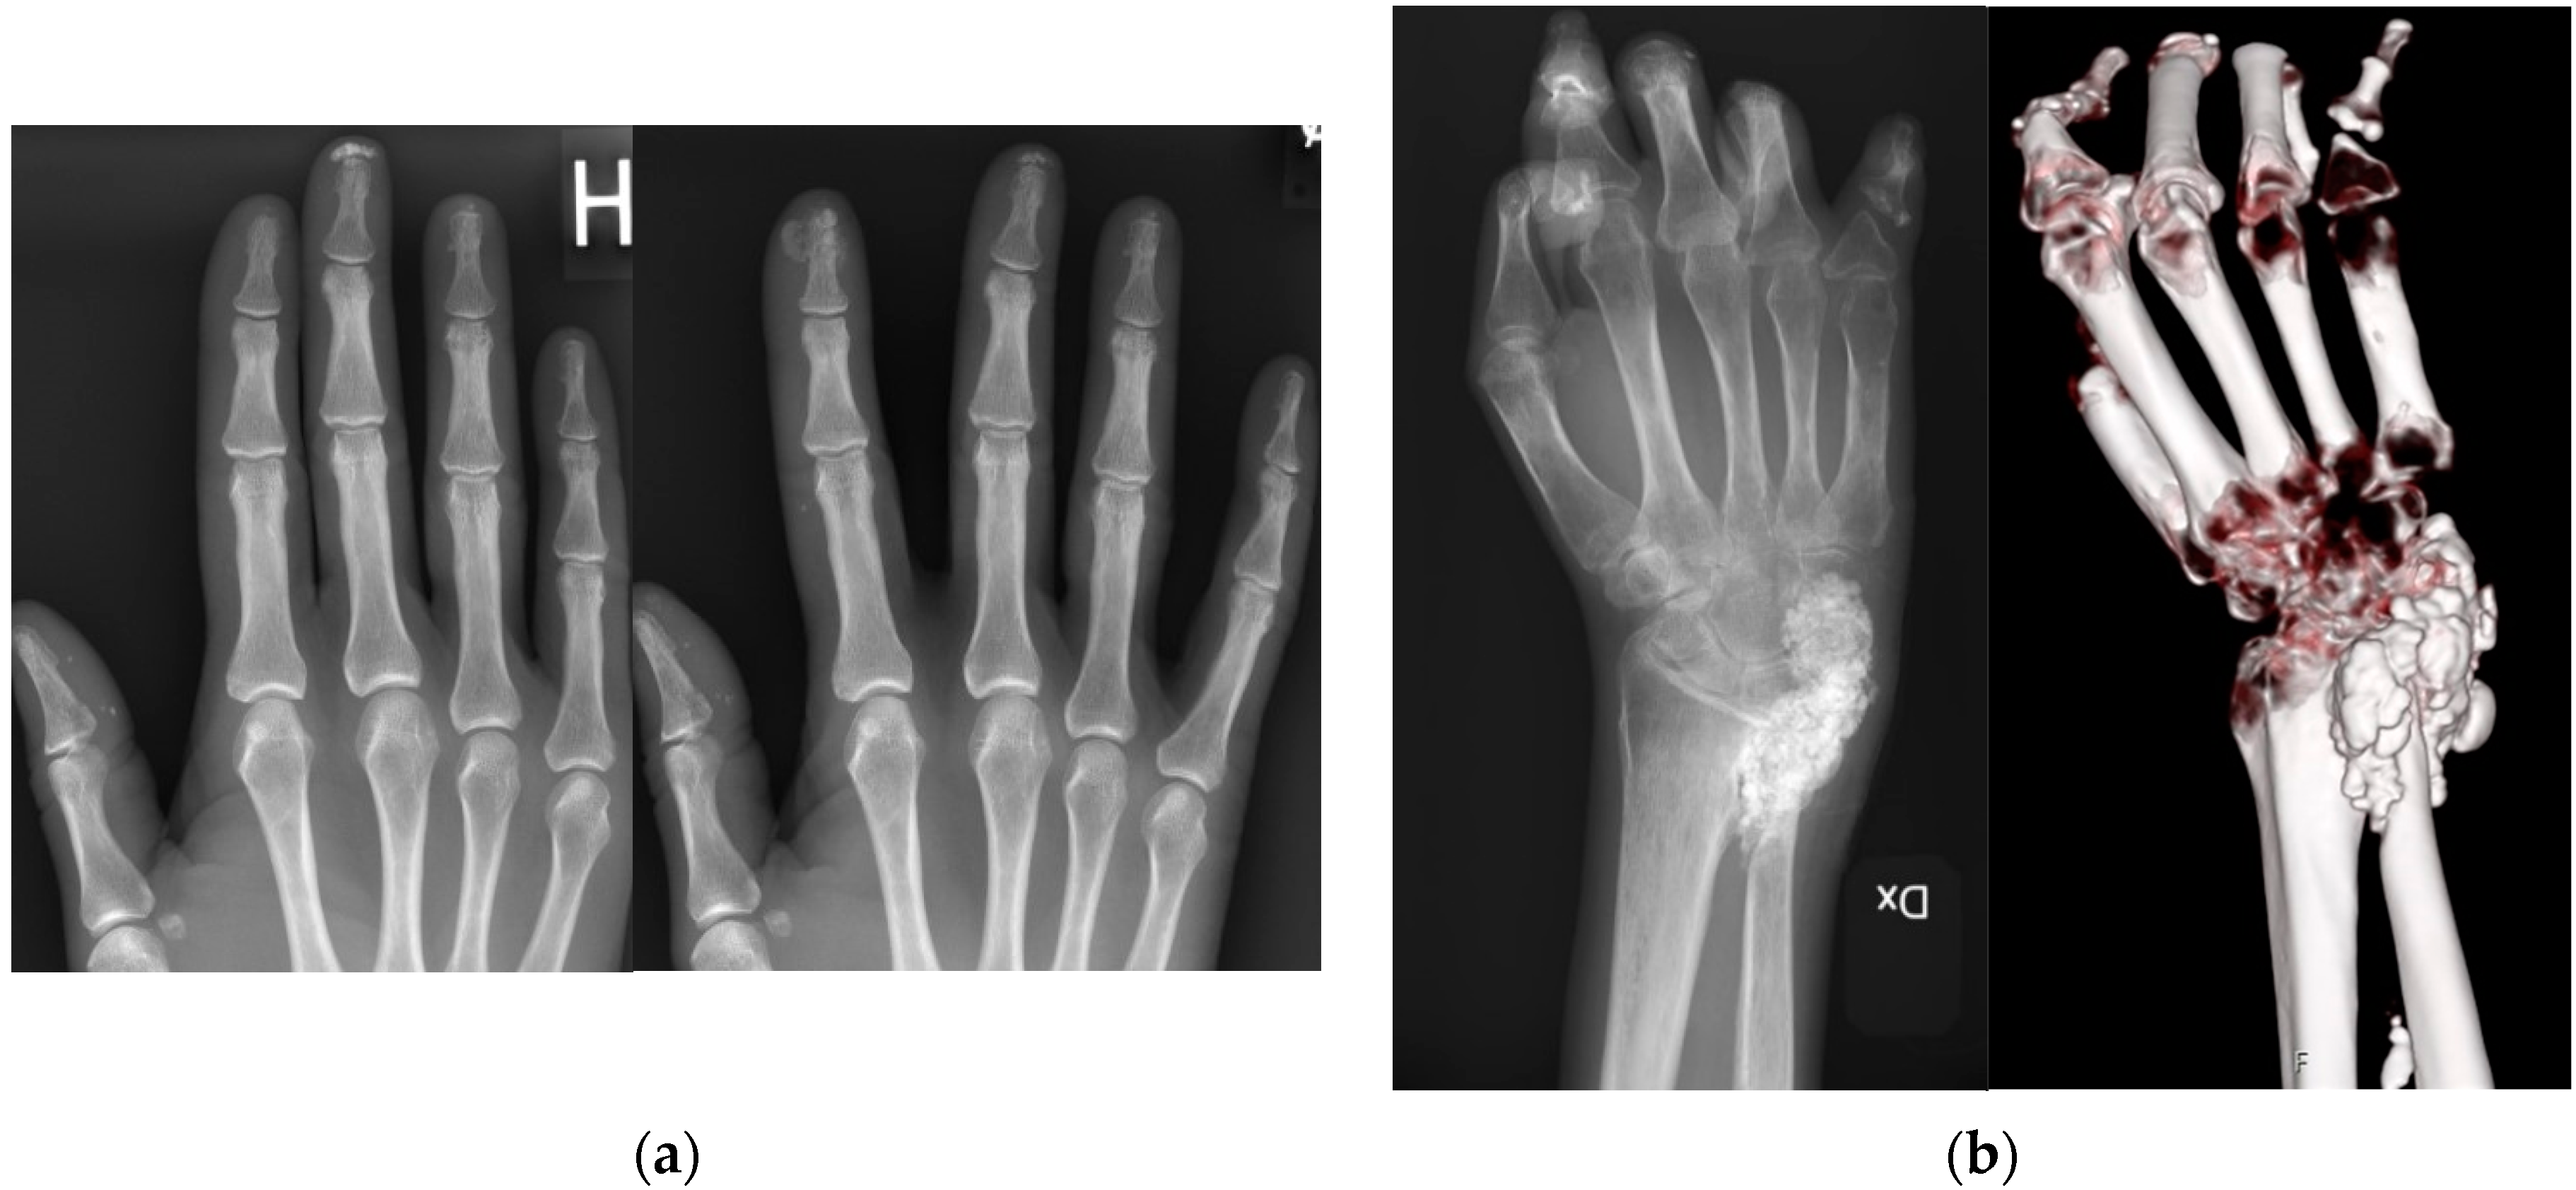

Figure 2. (a) Radiographic and computed tomography (CT) image of the same hand and wrist in a 48-year-old female Ssc patient. Conventional radiography showing multilobulated calcifications in the distal radioulnar joint and ulnar side of the wrist, measuring 3 × 5 × 2 cm. To the right, a CT 3D multiplanar visualization with bone algorithm. (b) Radiographic image of the hand of a 65-year-old female SSc patient showing calcinosis observed in the distal parts of the first, third, and fourth fingers of the right hand. On the right side, a new radiography examination four years later shows new calcinosis formation at the distal part of the second finger, with some deposits measuring up to 4 mm. Furthermore, reduced density of calcinosis at the distal end of the third finger.